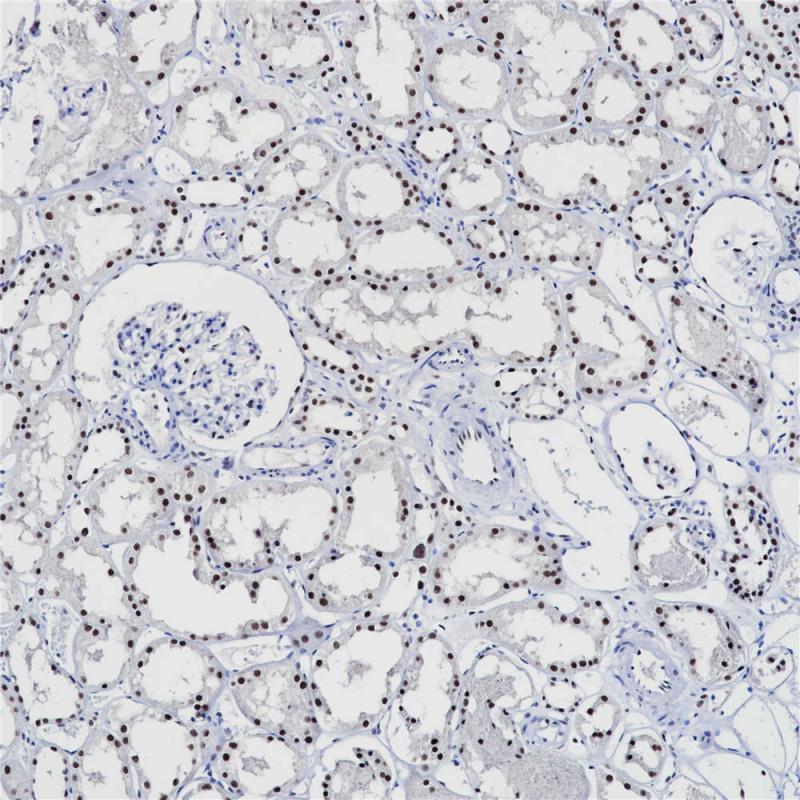

PMS2 重组兔单克隆抗体

PMS2是一种错配修复蛋白,这类的蛋白主要起到维持人体错配修机制稳定性,确保复制过程保真性的功能。这一蛋白通常用于结肠癌以判断其是否由于微卫星不稳定(microsatellite instability, MSI)机制所导致。PMS2抗体常用于Lynch综合征的免疫组化筛查。

亚细胞定位

细胞核